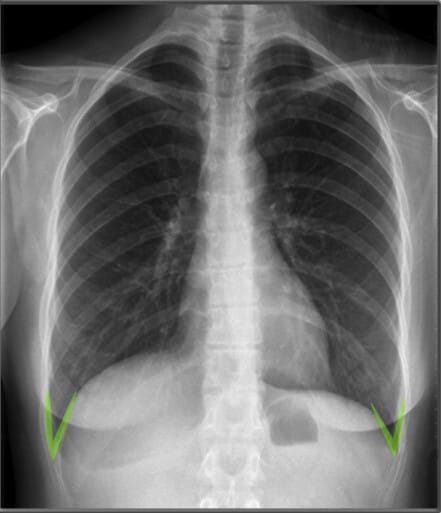

| 늑골횡격막각 (Costophrenic Angles) |

✅ 폐 하부와 횡격막이 만나는 부분으로, 정상적으로 뚜렷하고 날카로워야 합니다. ✅ 둔해지거나 소실되면 흉수(pleural effusion) 가능성을 시사합니다. |